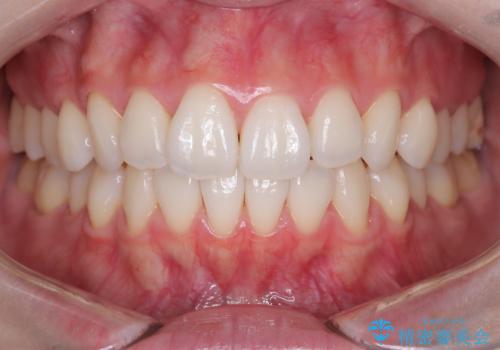

【インビザライン】前歯のねじれを治したい。

- 前歯の凸凹を主訴に来院されました。

スペースを作るために顎間ゴムを使用して、奥歯の遠心移動をおこない配列しました。

奥歯の遠心移動を行うことで、犬歯関係も良い状態に仕上げることができました。